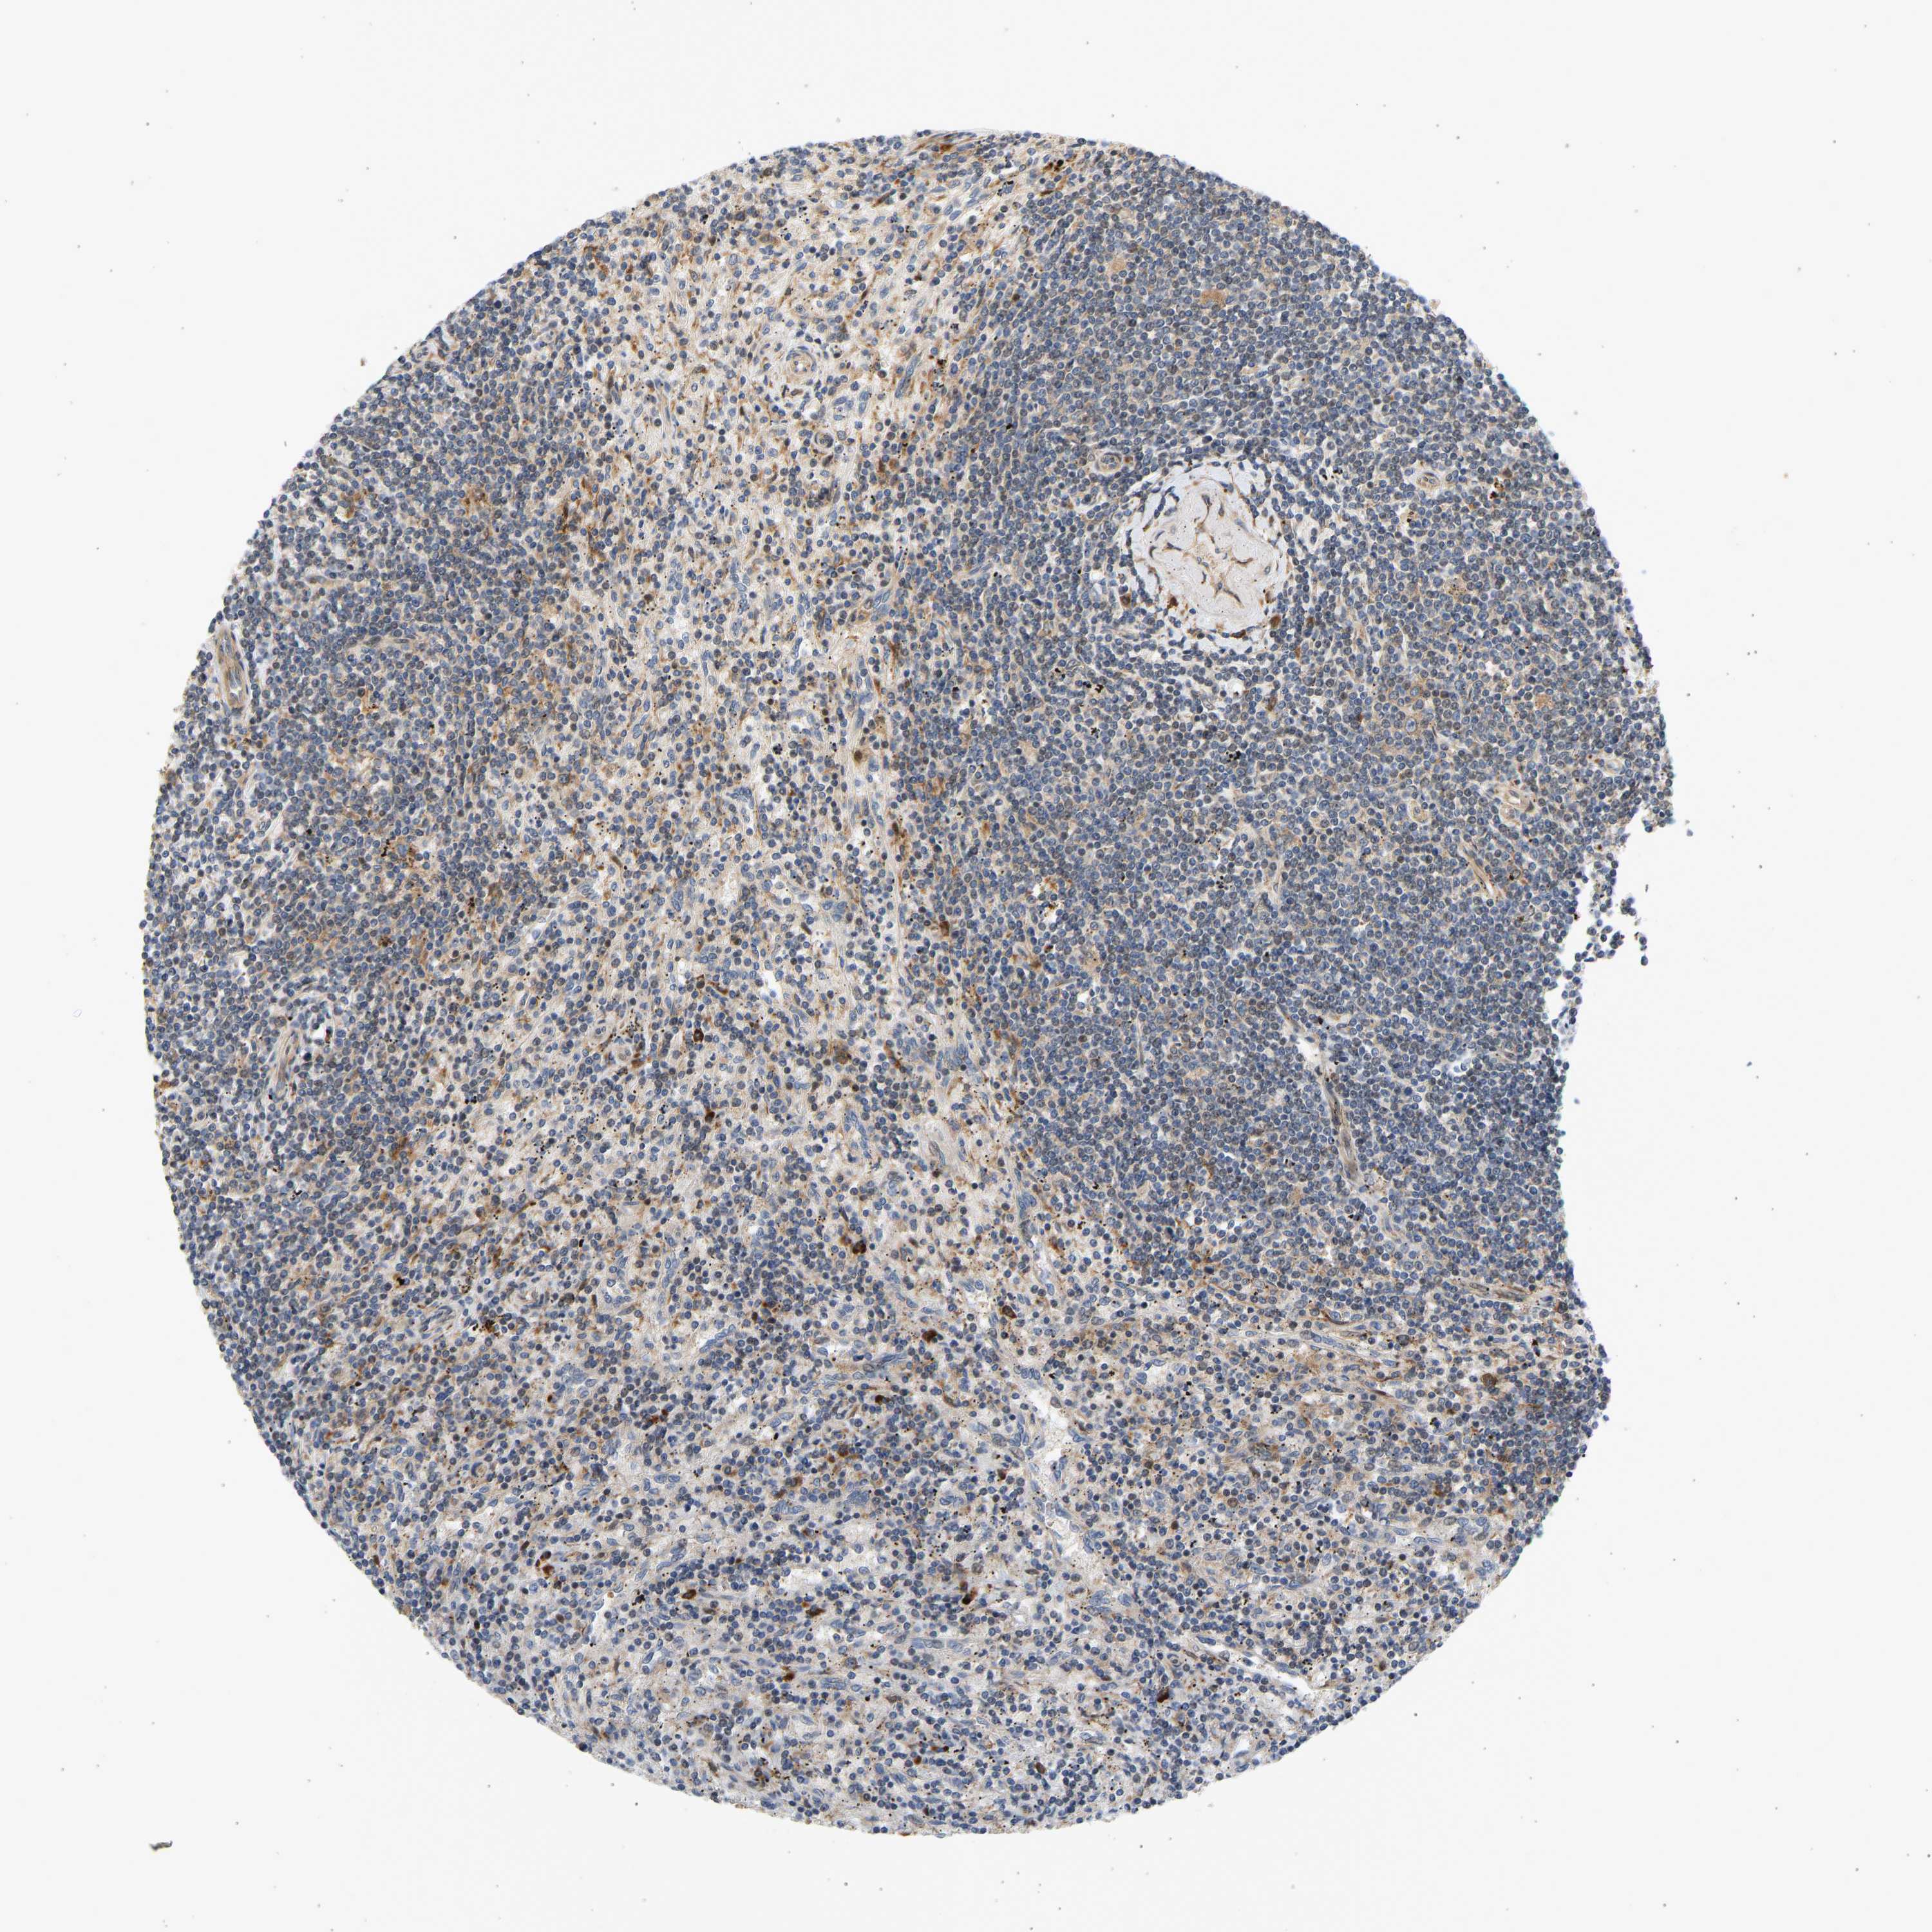

CANCER LYMPHOMA Show tissue menu

LYMPHOMA - Protein expressioni

A mouse-over function shows sample information and annotation data. Click on an image to view it in a full screen mode. Samples can be filtered based on level of antibody staining by selecting one or several of the following categories: high, medium, low and not detected. The assay and annotation is described here.

Each image is clickable and will lead to virtual microscopy that enables deeper exploration of all samples and also displays staining intensity scores, fraction scores and subcellular localization as well as patient and tissue information for each sample.

Antibody HPA018504

Staining

High

Medium

Low

Not detected

Intensity

Strong

Moderate

Weak

Negative

Quantity

>75%

75%-25%

<25%

None

Location

Nuclear

Cytoplasmic/membranous

Cytoplasmic/membranous,nuclear

Hodgkin's disease, NOS

Malignant lymphoma, non-Hodgkin's type, High grade

Malignant lymphoma, non-Hodgkin's type, Low grade